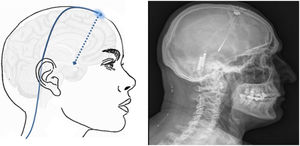

Estimulación trigeminal transcutánea: nervio supraorbitario (NSO)Modula la actividad nociceptiva a nivel del ganglio trigeminal y pueden tener acciones sobre el córtex cingulado anterior (fig. 1)21. Se ha evaluado en migraña:

Neuromodulación cerebral transcorticalTécnica: se localiza el área del dolor facial mediante RM, anterior a la cisura de Rolando, a nivel del surco frontal inferior. Con estos datos, el neuronavegador guiará la craneotomía bajo anestesia local o general. Después, se localiza el área de la mano mediante potenciales evocados intraoperatorios. Los electrodos, generalmente cuatro, inicialmente se implantaban a nivel subdural, pero en la actualidad, se sitúan a nivel epidural para evitar complicaciones (fig. 6). Tras verificar el correcto emplazamiento del dispositivo y el funcionamiento de la estimulación, se conectan los electrodos a un generador subclavicular mediante tunelización subcutánea del cableado142-145.

Esquema mostrando electrodos implantados en el área cortical motora a través de un orificio de trepanación frontal y cableado subcutáneo. A la derecha, radiografía craneal postcirugía que muestra los electrodos implantados en el córtex motor en un paciente con neuralgia del trigémino contralateral refractaria secundaria a esclerosis múltiple.